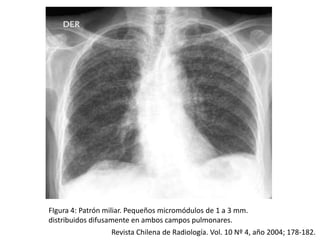

FIgura 4: Patrón miliar. Pequeños micromódulos de 1 a 3 mm.

distribuidos difusamente en ambos campos pulmonares.